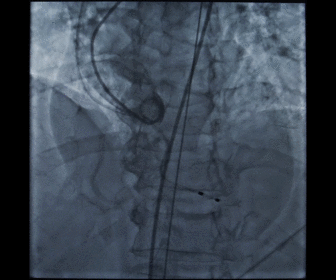

根部造影

球囊预扩